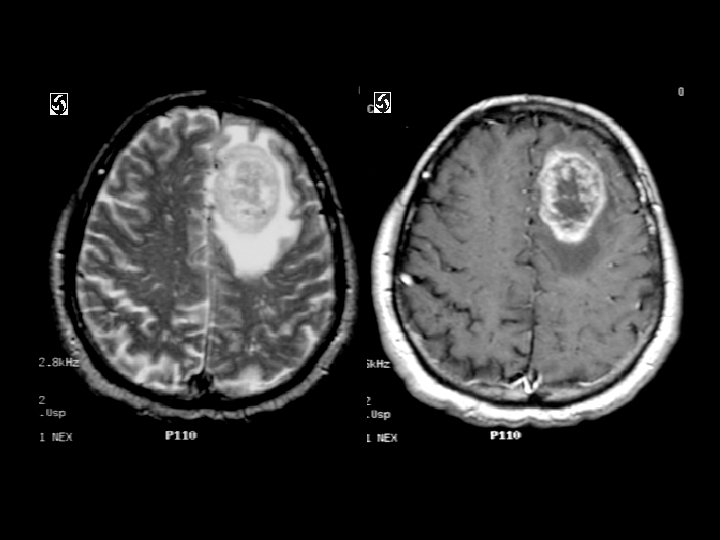

Glioblastoma multifome • Findings: – Aggressive intra-axial enchancing mass lesion with central necrosis • ddx: – Abscess – Tumafactive MS